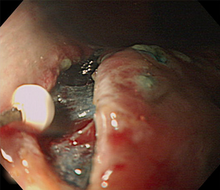

早期胃がんでは、お腹を切らずに内視鏡により切除するESD(内視鏡的粘膜下層切開剥離術) で治せるようになりました。内視鏡的技術と機器は著しく進歩しており、特にITナイフ、フレックスナイフ、フックナイフなどの処置具の登場、高周波発生装置の進化は内視鏡治療成績を上げています。

ESDとは、病変の周囲の粘膜を切開した後に粘膜下層を剥離して病変を切除する確実な内視鏡治療です。

従来のEMR(内視鏡的粘膜切除)という方法では小さな病変しか切除できませんでしたが、ESDは2cmをこえる大きながんの場合でも病変を一括に切除できる確実な内視鏡治療であり、癌の取り残しが少なく、再発する危険性もとても少ないです。

(1)がん病変を確認した後に、病変部に色素撒布をして、十分な観察を行って、切除範囲をマーキングします。

(2)周囲に局注し、プレカット(ITナイフを入れる小さな孔を作成)をします。

(3)マーキングした部位の外周を全周切開します。粘膜下に局注液を注入して病変部を盛り上げ、その粘膜下層を剥離して一括切除します。

(4)最後に切除した粘膜を回収して、病理組織学的に検索します。

このようにESD では大きな病変もひとかたまりでとれ、病理検査でのより正確な診断にも役立ちます。治療後は胃に人工的な潰瘍ができるため一週間の入院治療が必要です。退院後は内服と定期的な外来通院、内視鏡検査で経過をみます。ESD は患者さんの体にやさしく低侵襲性の内視鏡治療ですが、従来の治療法にくらべて技術習得が難しく、出血や穿孔といった合併症の頻度が少し高いことも事実です。当院では消化器内科医、外科医全員で診断・治療にあたっており、合併症に対しても十分な対策のうえに施行しています。